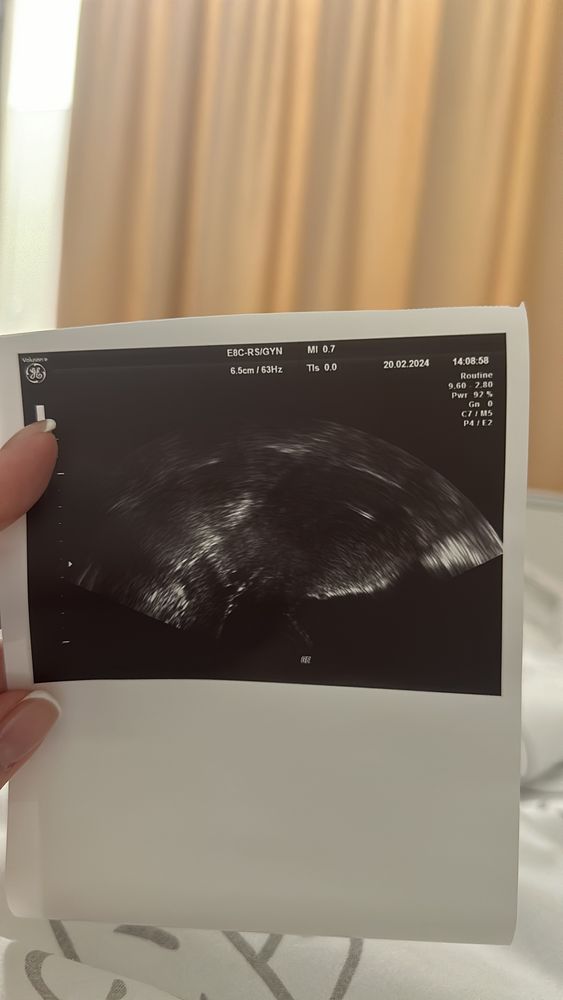

0 дпп, или 20.02 день надежды .

Эндометрий подрос🙏🏻 6день стимуляции